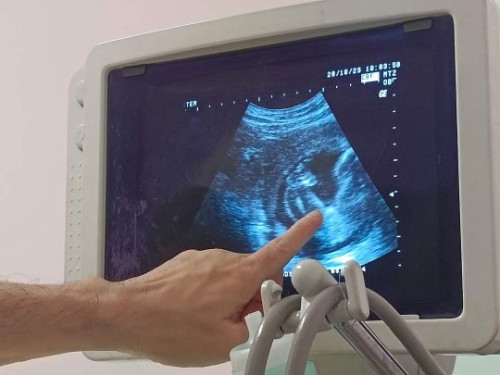

สอบถามความคิดเห็นแม่ๆ แบบนี้ผู้หญิงหรือผู้ชายค่ะ 24w คุณหมอบอก50/50 แต่ก็เหมือนจะผู้หญิงนะเดือนหน้ามาดูใหม่ เลยอยากมาถามแม่ที่มีประสบการณ์ เผื่อจะเป็นผู้ชายเข้าข้างตัวเอง 😄😊

น่าจะหญิงนะคะ